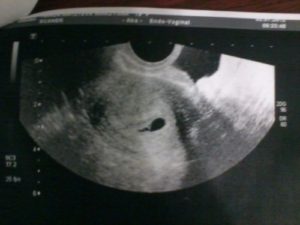

При одноплодной беременности на снимке различают темное околоплодное яйцо, которое имеет четкие, ровные границы и круглую или овальную форму. Его размер – 10 мм.

В плодном яйце заметен крошечный эмбрион (2–3 мм). На снимке он представляет собой пятно, напоминающее креветку или запятую, более светлого цвета. Если присмотреться, на картинке заметен желточный мешок (более темное пятно размером 4–6 мм) и не до конца сформировавшийся кишечник без характерных извилин.

При внематочной беременности околоплодное яйцо прикрепляется не к стенке матки, а к другому органу, например яичнику.